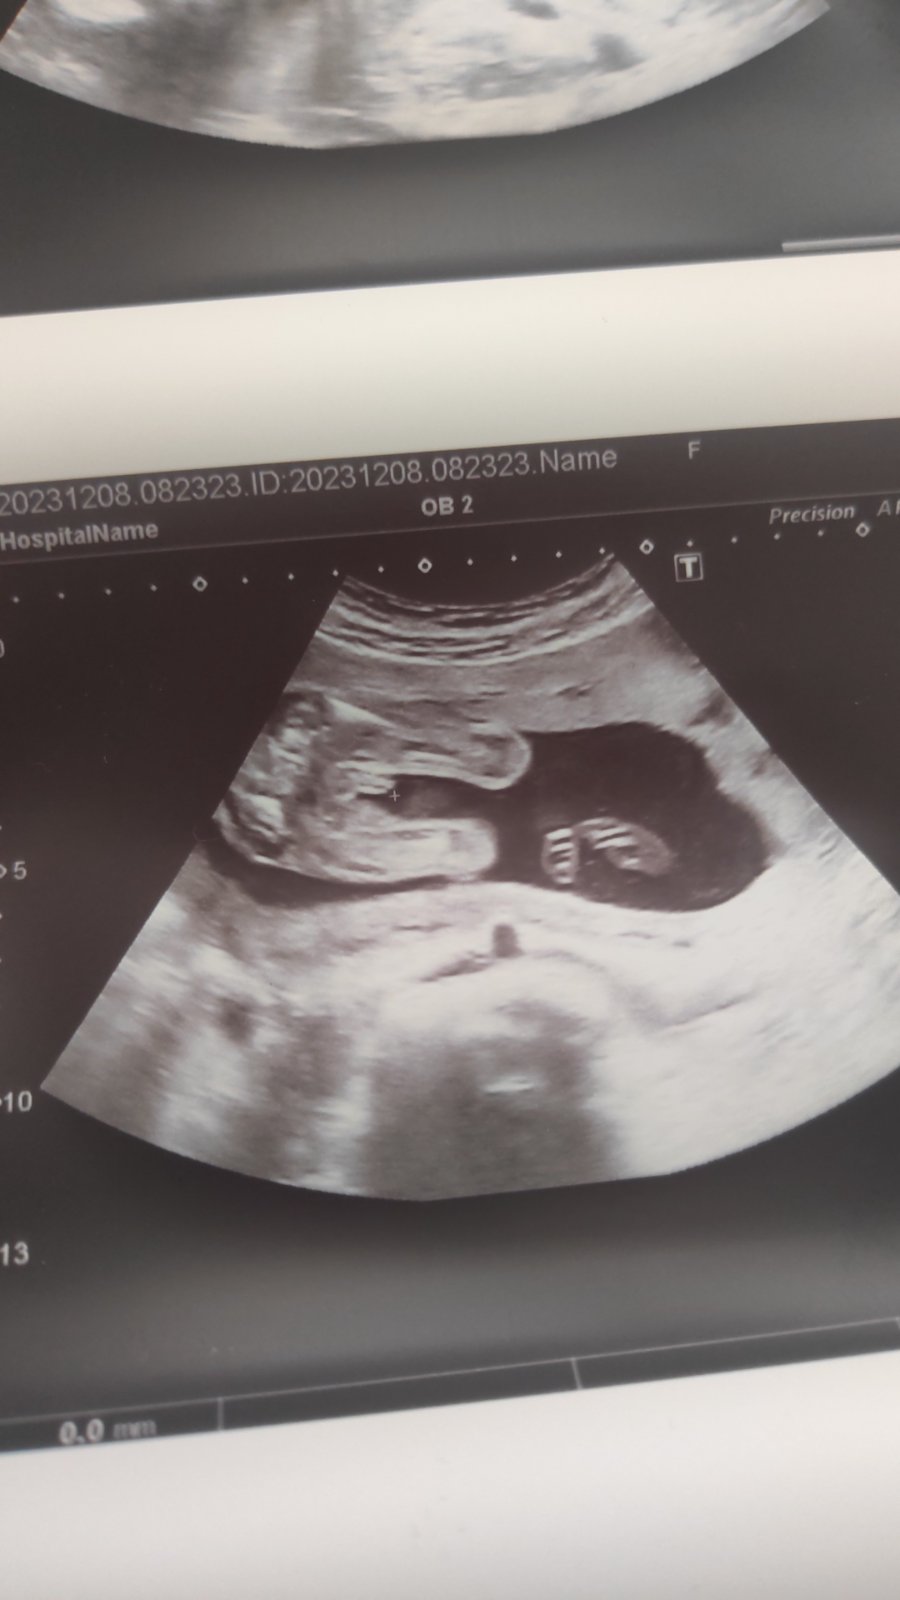

Mě teda tohle přijde k tělíčku dost jasně připojené v téhle úrovni řezu, tj zhruba ve výšce kyčlí... myslím, že je tam vidět i pytlík... Ale z naskenované fotky se mýlit můžu.